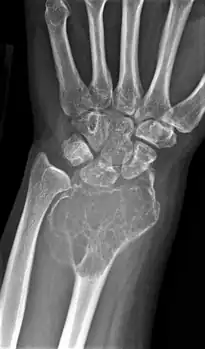

X-ray of a giant-cell bone tumor in the head of the fourth metacarpal of the left hand

Imaging

On X-ray, giant-cell tumors (GCTs) are lytic/lucent lesions that have an epiphyseal location and grow to the articular surface of the involved bone.[11] Radiologically the tumors may show characteristic 'soap bubble' appearance.[12] They are distinguishable from other bony tumors in that GCTs usually have a nonsclerotic and sharply defined border. About 5% of giant-cell tumors metastasize, usually to a lung, which may be benign metastasis,[13] when the diagnosis of giant-cell tumor is suspected, a chest X-ray or computed tomography may be needed. MRI can be used to assess intramedullary and soft tissue extension.